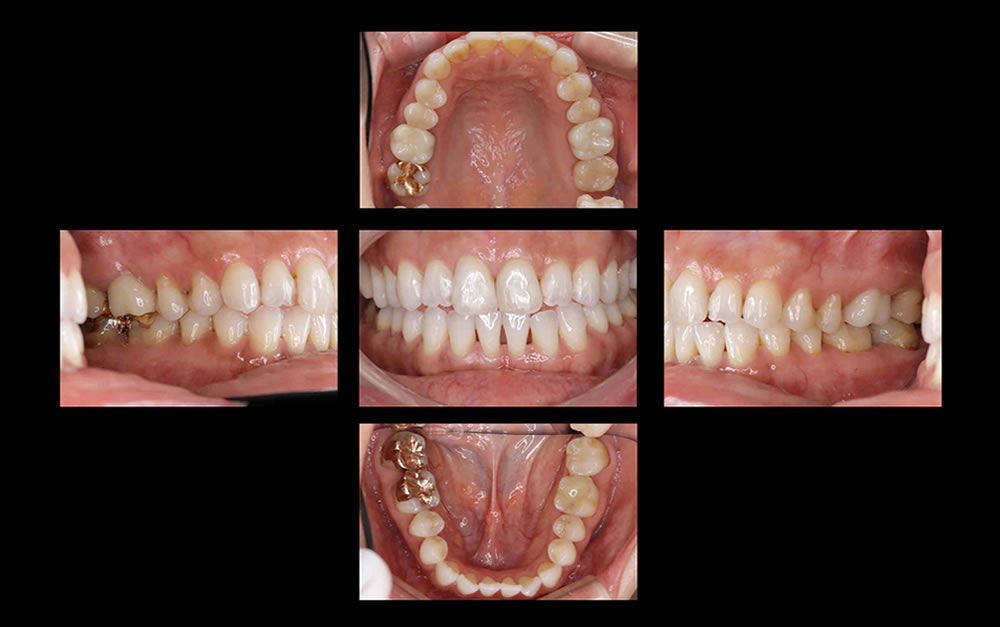

口腔内写真(5枚法)

初診では、口腔内写真を5枚法で撮影します。治療経過を見ていく上で、有用な記録となります。